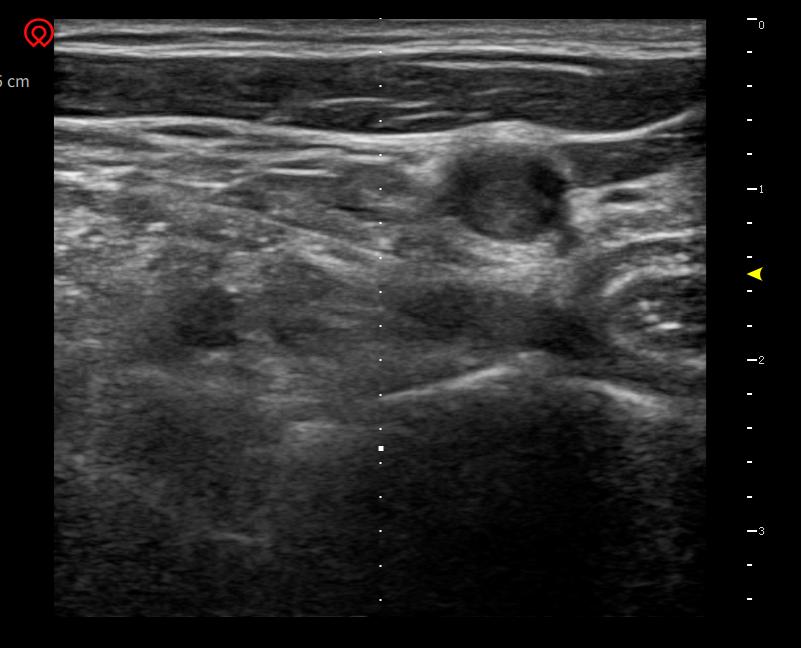

对于不想做手术的患者,可以采取超声引导下神经阻滞。B超不只是一种检查手段,更是一种治疗工具。在超声引导下,可以清晰看到病变神经、穿刺针的位置,做到精准治疗,提高有效率,减少并发症。